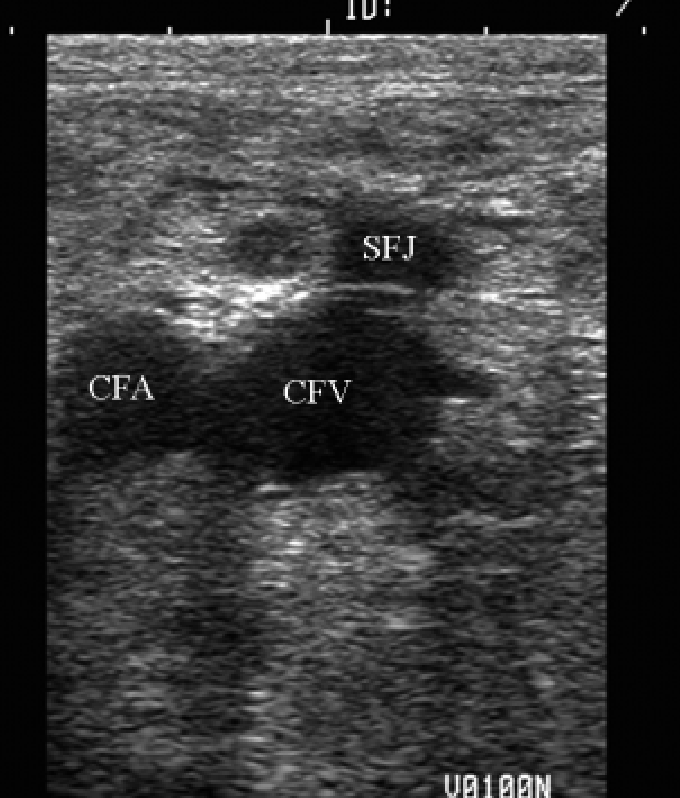

- 股動靜脈超音波示意圖 (圖6)

(圖6)

股靜脈(femoral vein): 將大腿彎曲成青蛙腿的擺位(圖4) , 可以將動靜脈之間相差的角度拉大, 比較不容易overlapping(紅線動脈/藍線靜脈) , 接著根據解剖構造, 動脈內側約一公分即為股靜脈所在的位置(圖5) , 完成定位,可進行超音波掃描